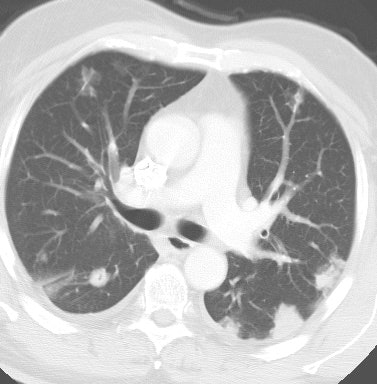

Bronchoalveolar cell carcinoma presenting at multiple poorly marginated lung nodules- some of which appear cavitary. The findings mimic a pulmonary infectious process. |